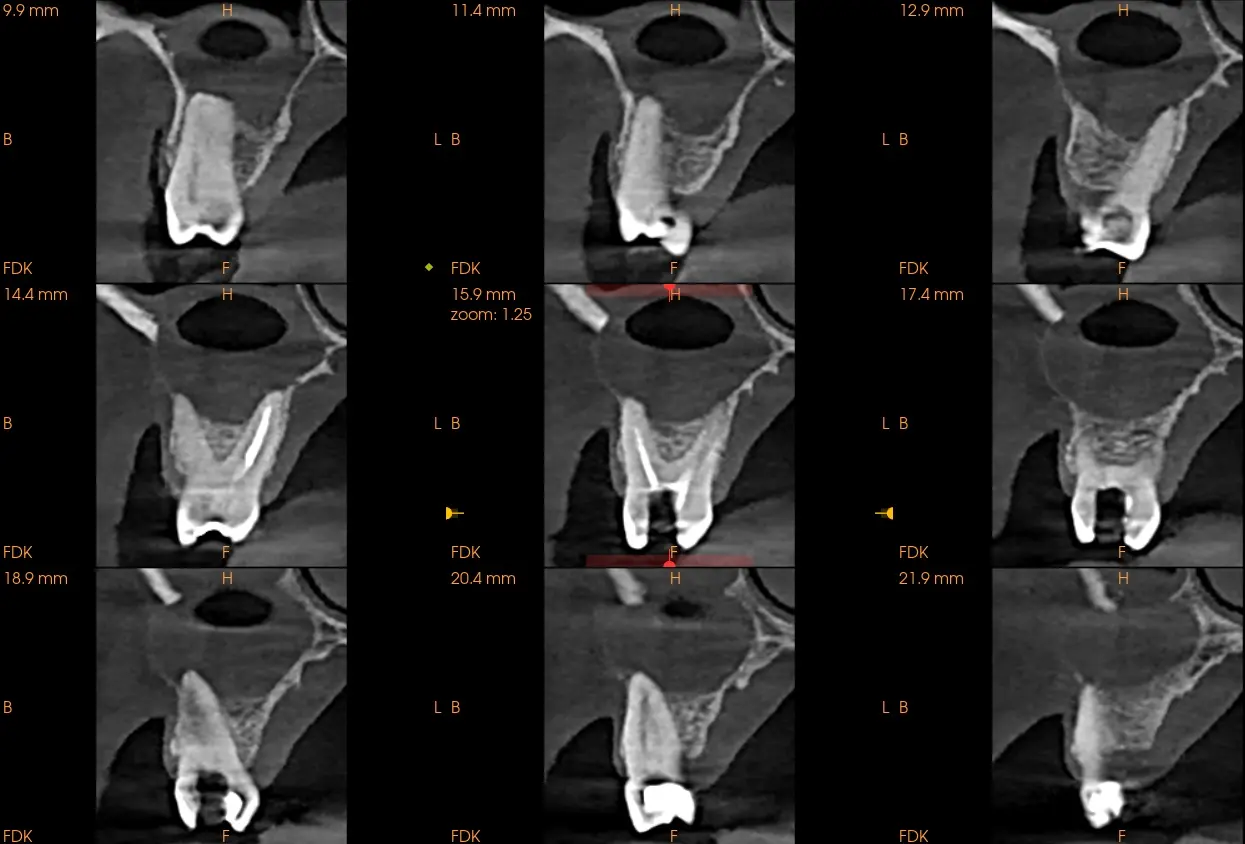

Estudio solicitado: Tomografía Cone Beam de un maxilar completo

Al realizarle la tomografía se evidencia de manera general dientes con tratamientos de conductos que no llelgan al limite CDC (Ver imagen 1 panorámica). En zona de Pd 16 se ve imágen hipodensa , de carácter expansivo que empuja las zonas adyacentes y el seno maxilar, generando una disminución del reborde óseo tanto palatino como vestibular, se observa que la pieza dental 16 presenta tratamiento de conducto, esta lesión genera también un engrosamiento de la membrana sinusal (posible quiste de retención mucosa) y disminución o posible ausencia del piso sinusal. Sobre la misma se observa en la imagen N°6 que presenta los cortes trasnaxiales, una cavidad de aire en dicho quiste periapical. Posiblemente debido a una interacción con las bacterias sinusales. En la cavidad sinusal se observa el pólipo sinusal de la cavidad derecha.

También en zona hemimaxilar izquierda se descubrió una lesión periapical en pieza dental 26, la raíz vestibulo mesial. que genera un leve engrosamiento de la membrana sinusal y fenestracion de tabla vesticular. (imagen 5)